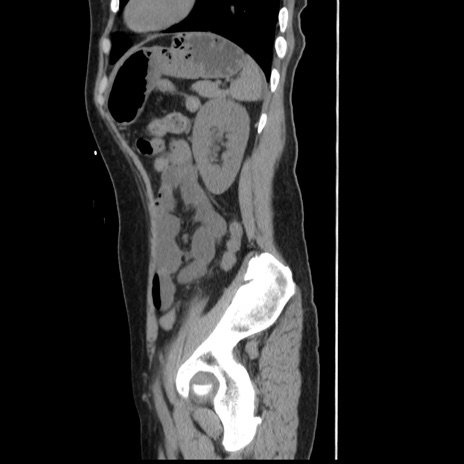

症例10(矢状断像)

【症例】 50歳代女性

【主訴】 腹痛

【現病歴】前日生レバーを食べた。今朝に排便あり。 昼前に突然発症の腹痛を生じ、当院救急外来を受診した。

【既往歴】 子宮筋腫にてで子宮全摘後

【身体所見】 意識清明、腹部:平坦、軟、下腹部やや左を中心に圧痛・反跳痛あり、筋性防御あり

【データ】WBC 7800、CRP 0.07